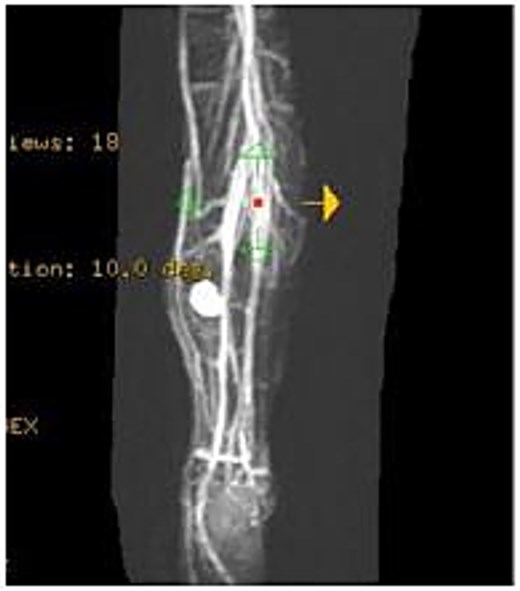

A 4-year-old boy presented with swelling on the medial aspect of his left leg. Three months prior, the patient had sustained a left tibial shaft fracture, initially treated conservatively. The swelling developed gradually with localized tenderness. On examination, the swelling was firm and tender to palpation, with intact overlying skin (Fig. 1). Radiography revealed erosion of the tibia (Fig. 2). Given the patient's fracture history, the initial differential included osteomyelitis, and empirical antibiotics were started. The vascular surgery team suspected a pseudoaneurysm and recommended further evaluation. Doppler ultrasound confirmed a pseudoaneurysm, revealing an abnormal vascular structure with turbulent blood flow. To delineate the vascular anatomy and identify the pseudoaneurysm's origin, magnetic resonance angiography (MRA) was ordered. It demonstrated the pseudoaneurysm arising from an unnamed posterior tibial artery branch, likely injured during initial trauma. The aneurysmal sac was located near the fracture site, eroding the underlying tibial bone (Fig. 3). The pseudoaneurysm's size warranted surgical intervention. The patient underwent excision of the aneurysmal sac and vessel wall repair (Fig. 4). Under general anesthesia, the aneurysmal sac was dissected out (Fig. 5), and the posterior tibial artery wall was repaired with lateral sutures. Hemostasis was achieved, and the wound was closed in layers. The patient had an uneventful postoperative recovery.

MRA showing the pseudoaneurysm arising from an unnamed branch of the posterior tibial artery.

Ultrasound is a key diagnostic tool for aneurysms [16]. It is non-invasive, cost-effective, and requires no contrast or sedation in pediatric patients [17]. Ultrasonography can accurately locate posterior tibial artery aneurysms and detect mural thrombi [18]. In our case, Doppler ultrasound confirmed the pseudoaneurysm and helped assess perfusion for perioperative decisions. MRA and computed tomography angiography are alternative imaging options [4, 17]. Our MRA showed the pseudoaneurysm near the fracture site, eroding the tibial bone, originating from a posterior tibial artery branch. Treatment options include arterial repair, graft interposition, ligation, compression, thrombin injection, and endovascular intervention [6]. With no standard protocol for post-traumatic posterior tibial artery pseudoaneurysms, surgical repair is preferred over conservative treatment due to embolization risks [10]. The patient underwent aneurysmal sac excision and vessel wall repair.